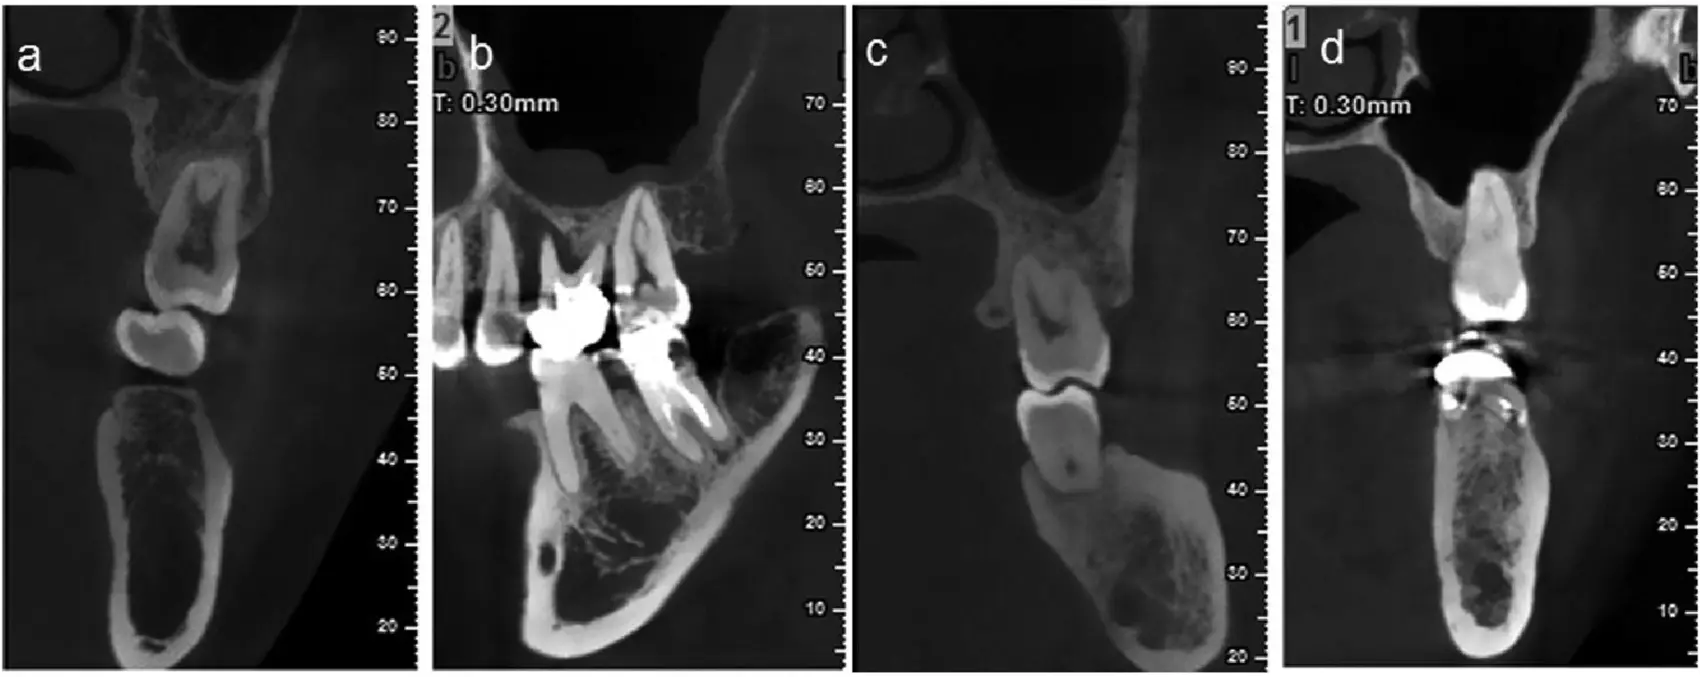

Access Endodontics is proud to announce the addition of a cone-beam computed tomography (CT) to our practice. This advanced technology allows Dr. Lee to use this special type of x-ray equipment when regular dental or facial x-rays are not sufficient.

Cone-beam computed tomography (CBCT), also referred to as a CT, is a medical imaging technique consisting of X-ray computed Tomography.